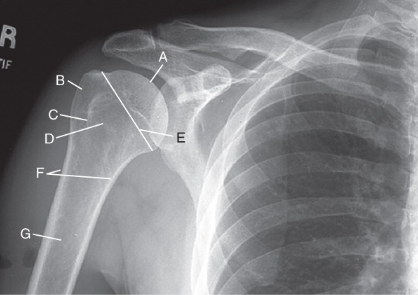

label the anatomy accordingly A-G, the projection/part, and rotation if applicable

head of humerus, greater tubercle, intertubercular sulcus, lesser tubercle, anatomic neck, surgical neck, body

AP shoulder — external rotation